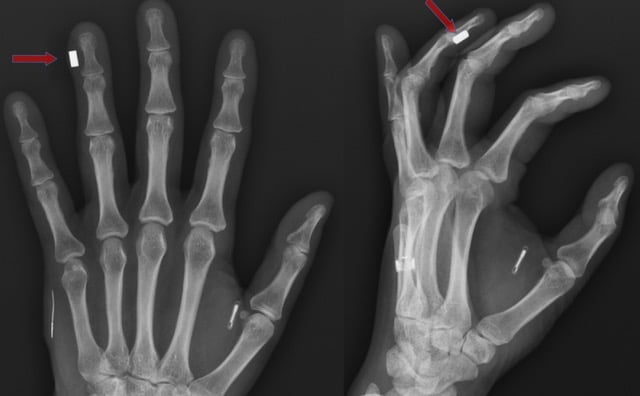

The microchips, which use Near Field Communication (NFC) technology similar to that found in contactless payment cards, are typically implanted between the thumb and forefinger. Users can simply wave their hands near scanners to unlock office doors, access gym facilities, pay for train tickets, and even make purchases at cafes and restaurants.

X-ray image (18 February 2022) — photo by Sandra W, licensed under CC BY-SA 4.0.